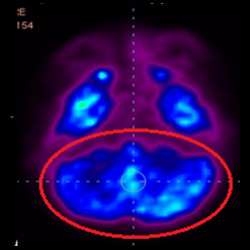

細胞治療前PET CT掃描顯示神經(jīng)組織中的藍/黑色區域,表明腦癱引起的大腦損傷。

細胞治療后,藍色和黑色區域減少,并且看到更活躍的區域。這表明損傷減少并改善了大腦功能。